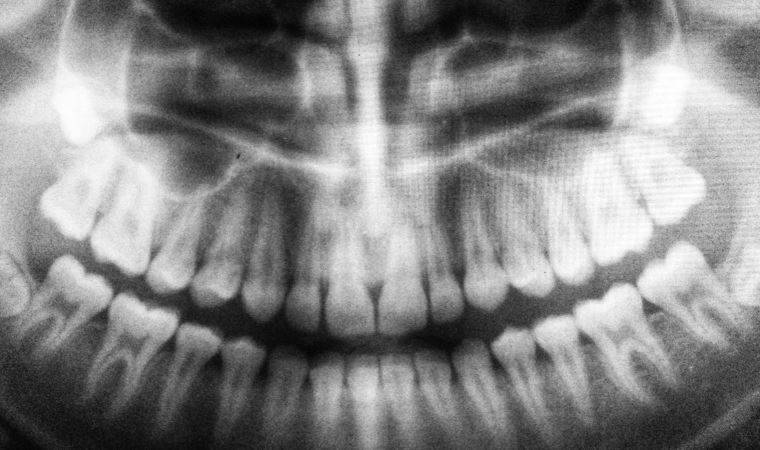

Halk arasında diş sıkma ve diş gıcırdatma olarak bilinen bruksizmin bazı hastalıkların da habercisi olduğuna dikkat çeken Dr. Ergül, “Bruksizm yani diş sıkma ve diş gıcırdatma durumu, bireyin dişlerinin istemsizce birbirine sürttüğü durumlara deniyor. Her 4 çocuktan birinde görülebiliyor ve okul öncesi çocuklarda bunun daha fazla olduğunu biliyoruz. Bruksizm, stres ve depresif ruh hali gibi sebeplerden kaynaklanabileceği gibi dişlerdeki çapraşıklıklar, çürük, apse veya yüksek dolgulardan da kaynaklanabilir” dedi.

Dr. Ergül çocuklarda görülen bruksizmin tedavi edilmediği takdirde, eğer sorun diş kaynaklı ise dişlerde aşınmalara, çene kemiği rahatsızlıklarına ve uyku problemlerine sebep olarak yine çocuğun yaşam kalitesinin olumsuz etkilendiğini söyledi.